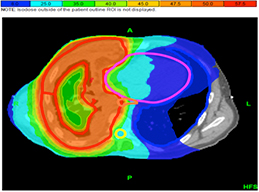

Η ακτινοθεραπεία χρησιμοποιεί υψηλής ενέργειας ακτίνες Χ, για να σκοτώσει τα καρκινικά κύτταρα. Οι κυριότερες τεχνικές ακτινοθεραπείας που χρησιμοποιούνται είναι η εξωτερική ακτινοθεραπεία που αποτελείται από τη τρισδιάστατη σύμμορφο ακτινοθεραπεία (3D-CRT), τη διαμορφούμενης έντασης ακτινοθεραπεία ( IMRT) και την απεικονιστικά καθοδηγούμενη ακτινοθεραπεία( IGRT).Σε όγκους σταδίου Ι,ΙΙ χρησιμοποιείται η στερεοτακτική ακτινοθεραπεία με αποτελέσματα ισάξια της χειρουργικής αφαίρεσης. Αυτή η μορφή της ακτινοβολίας στοχεύει πολλές ακτίνες ακτινοβολίας από διαφορετικές γωνίες στο καρκίνο του πνεύμονα. Η θεραπεία ολοκληρώνεται σε 1-3 συνεδρίες.

|

![]() |